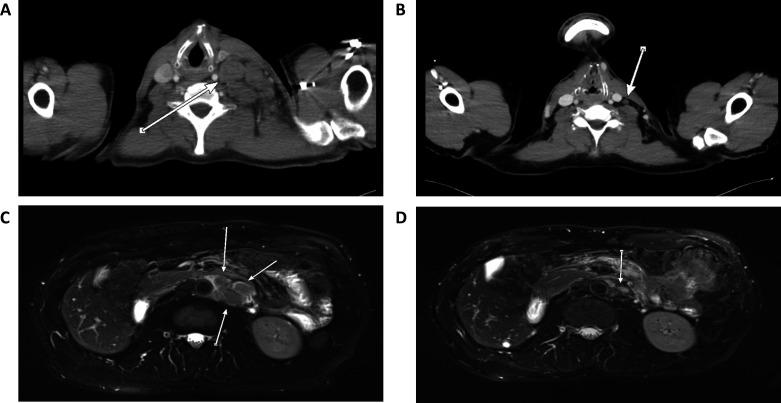

Upper tract urothelial carcinoma (UTUC) is often diagnosed late and exhibits poor prognosis. Only limited data are available concerning therapeutic regimes and potential biomarkers for disease monitoring. Standard therapies often provide only insufficient treatment options. Hence, immunotherapies and complementary approaches, such as personalized neoepitope-derived multipeptide vaccine (PNMV), come into focus. In this context, genetic analysis of tumor tissue by whole exome sequencing represents an essential diagnostic step in order to calculate tumor mutational burden (TMB) and to reveal tumor-specific neoantigens. Furthermore, disease progression is essential to be monitored. Longitudinal screening of individually known mutations in plasma circulating tumor DNA (ctDNA) by the use of next-generation sequencing and digital droplet PCR (ddPCR) might be a promising method to fill this gap.Here, we present the case of a 55-year-old man who was diagnosed with high-risk metastatic UTUC in 2015. After initial surgery and palliative chemotherapy, he developed recurrence of the tumor. Genetic analysis revealed a high TMB of 41.2 mutations per megabase suggesting a potential success of immunotherapy. Therefore, in 2016, off-label treatment with the checkpoint-inhibitor pembrolizumab was started leading to strong regression of the disease. This therapy was then discontinued due to side effects and treatment with a previously produced PNMV was started that induced strong T cell responses. During both treatments, plasma Liquid Biopsies (pLBs) were performed to measure the number of mutated molecules per mL plasma (MM/mL) of a known tumor-specific variant in the gene by ddPCR for longitudinal monitoring. Under treatment, MM/mL was constantly zero. A few months after all therapies had been discontinued, an increase of MM/mL was detected that persisted in the following pLBs. When MRI scans proved tumor recurrence, treatment with pembrolizumab was started again leading to a rapid decrease of MM/mL in the pLB to again zero. Treatment response was then also confirmed by MRI.This case shows that use of immunotherapy and PNMV might be a promising treatment option for patients with high-risk metastatic UTUC. Furthermore, measurement of individually known tumor mutations in plasma ctDNA by the use of pLB could be a very sensitive biomarker to longitudinally monitor disease.

上尿路尿路上皮癌(UTUC)常被诊断为晚期,预后较差。目前关于治疗方案和疾病监测的潜在生物标志物的相关数据非常有限。标准疗法通常只能提供有限的治疗选择。因此,免疫疗法和补充疗法,如个性化新抗原衍生的多肽疫苗(PNMV),成为关注的焦点。在这种情况下,通过全外显子组测序对肿瘤组织进行基因分析是计算肿瘤突变负担(TMB)并揭示肿瘤特异性新抗原的重要诊断步骤。此外,疾病的进展是必须要监测的。通过使用下一代测序和数字液滴 PCR(ddPCR)对血浆循环肿瘤 DNA(ctDNA)中个体已知突变进行纵向筛查,可能是一种很有前途的方法来填补这一空白。在此,我们报告了一位 55 岁男性的病例,他于 2015 年被诊断为高危转移性 UTUC。在初始手术和姑息性化疗后,他的肿瘤复发。基因分析显示 TMB 为 41.2 个突变/兆碱基,提示免疫治疗可能有效。因此,2016 年,开始使用免疫检查点抑制剂派姆单抗进行非适应证治疗,导致疾病明显缓解。由于副作用,该治疗随后被停止,并开始使用之前生产的 PNMV,该药物诱导了强烈的 T 细胞反应。在两种治疗过程中,均进行了血浆液体活检(pLB),通过 ddPCR 测量基因中已知肿瘤特异性变体的每毫升血浆中的突变分子数(MM/mL),进行纵向监测。在治疗期间,MM/mL 始终为零。在所有治疗停止后几个月,检测到 MM/mL 增加,且在随后的 pLB 中持续存在。当 MRI 扫描证实肿瘤复发时,再次开始使用派姆单抗治疗,导致 pLB 中的 MM/mL 迅速下降至零。然后通过 MRI 确认了治疗反应。该病例表明,免疫疗法和 PNMV 的联合应用可能是高危转移性 UTUC 患者的一种有前途的治疗选择。此外,使用 pLB 测量血浆 ctDNA 中的个体已知肿瘤突变可能是一种非常敏感的生物标志物,可用于纵向监测疾病。